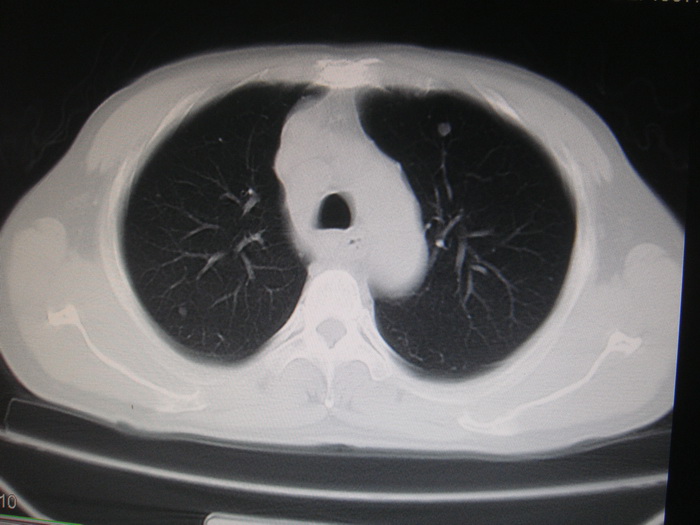

两肺多发结节灶及纵膈淋巴结肿大考虑为转移

两肺多发性转移瘤,纵隔淋巴结转移。

两肺多发性转移瘤,前上纵隔淋巴结转移。

颈部肿块也可能是转移。